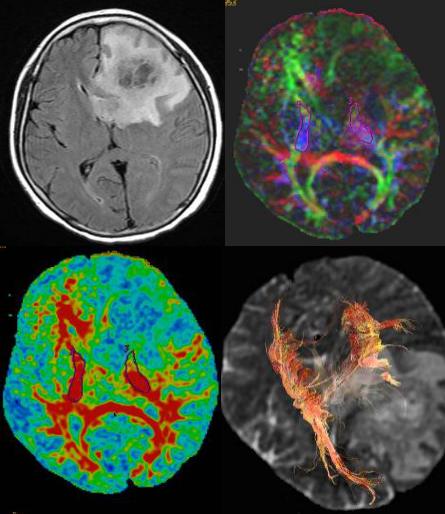

脑肿瘤应用

DTI可以定量分析肿瘤组织特点以鉴别肿瘤的级别,鉴别正常的白质纤维、水肿及肿瘤区域;显示神经纤维束与脑肿瘤的关系,使临床外科医生可以在术前、术中更清楚掌握肿瘤和白质纤维的情况,使手术方案更加可靠安全,并评估预后,这是DTI技术最有临床价值和应用的前景。

有学者利用FA图和彩色张量图将肿瘤和白质纤维的关系分为4种模式。

模式I:患侧纤维的FA值相对于对侧正常或轻微降低(降低<25%)同时纤维的位置或/和方向发生改变。

模式I,为肿瘤挤压周围纤维移位,提示肿瘤为良性或侵袭性不强的恶性肿瘤

模式II:患侧纤维FA值相对于对侧明显降低(>25%),同时纤维位置和方向正常。

模式II提示瘤周发生水肿,但不排除有肿瘤侵入。

模式III:患侧纤维FA值相对于对侧明显减低,同时纤维的走向发生改变。

模式III提示瘤周纤维被肿瘤侵入

模式IV:患侧纤维显示各向同性或近似同性,无法看出走行方向。

模式IV,提示肿瘤破坏瘤周纤维,仅限于恶性肿瘤,但可以是高级别或低级别肿瘤

这四种模式对应不同的手术方案。模式I和模式IV建议肿瘤全切,模式II和模式III建议部分切除,加强辅助治疗,提高生存质量。

左侧颞部脑膜瘤DTI示左侧神经纤维束受压移位,但连续性完整,符合模式I

左侧额叶低级别胶质瘤,低灌注,左侧额叶白质纤维破坏,无法看出走行,符合模式IV